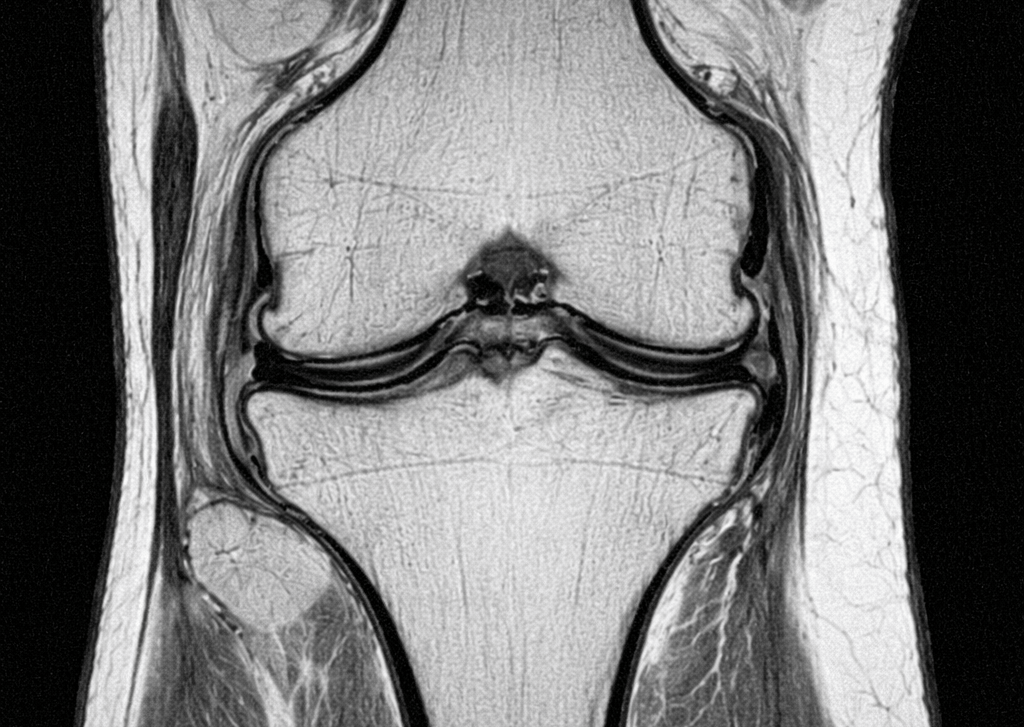

L’IRM du genou est un examen d’imagerie médicale qui permet d’analyser en détail les structures internes du genou.

L’IRM (Imagerie par Résonance Magnétique) est un examen qui utilise un champ magnétique pour obtenir des images précises du genou.

Elle permet de visualiser :

les ménisques

les ligaments

le cartilage

les tendons

l’os

Contrairement à la radiographie, elle permet d’explorer les tissus mous.

Que montre une IRM du genou

L’IRM permet de détecter :

lésions du ménisque

rupture des ligaments

arthrose du genou

inflammation articulaire

épanchement de synovie

C’est un examen très précis pour le diagnostic.